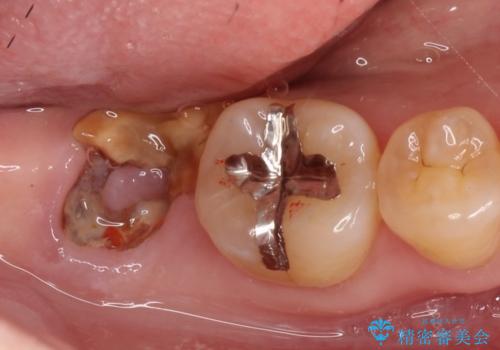

【インプラント】虫歯が大きくて歯を抜いた。

- 奥歯の虫歯が大きいため保存不可となった患者様です。

矯正の治療も進めながら、インプラントを埋入して補綴をおこなっています。